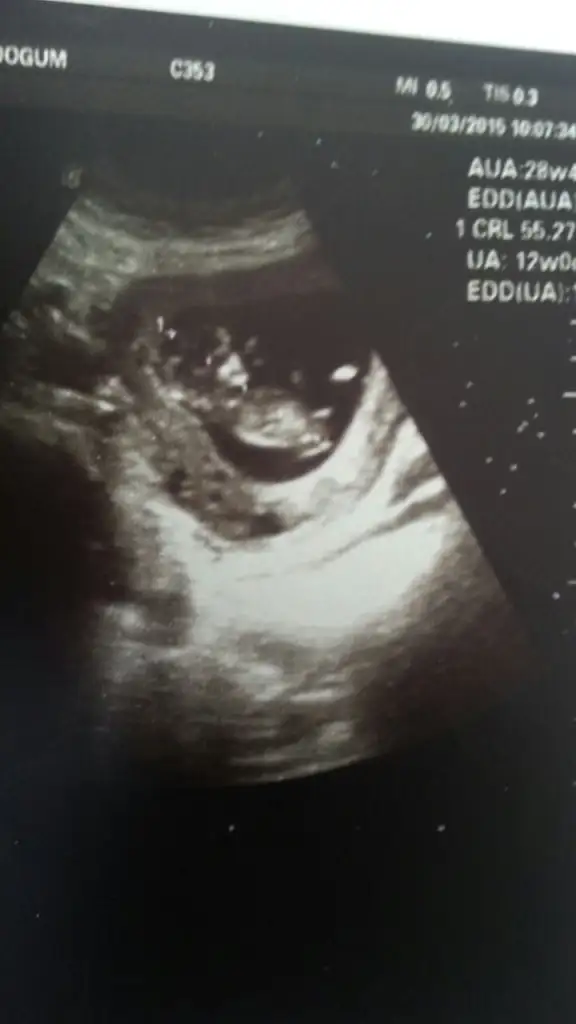

Slm buna bakarmisiniz arkadaslar tahminlerinizi bekiyorum.

• IMG-20150330-WA0001.webp

12,8 KB · Görüntüleme: 110

• IMG-20150330-WA0000.webp

11,8 KB · Görüntüleme: 111

Ay canım erkek sankii :) Tecrübeli arkadaşlar daha net söylerler. O çıkıntı eğer kordon değil de nubsa baya yukarı doğru sanki :) Sağlıkla gelsin inşallah

Bence kordon canım benim bebeğimden biliyorum benimkide hep öyle duruyo. Ama tecrübeli arkadaşlar daha iyi bilir :)